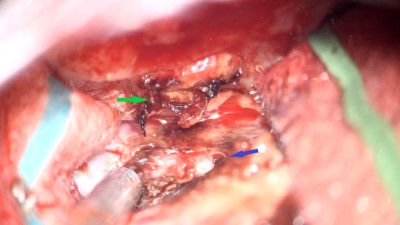

Intraoperative photo demonstrating the operative approach. A right temporal craniotomy has been made and the covering of the brain, the dura mater, is being dissected off of the base of the skull. Orientation: this is the right side of the head; the ear is just off the top of the frame (green star(*)), the nose is to the left, the back of the head the right, and the top of the head is toward the bottom.

Intraoperative video demonstrating the dissection of the encephalocele. Note the band of tissue extending from the skull base defect on the top of the image through the dural defect toward the bottom. This is the encephalocele.